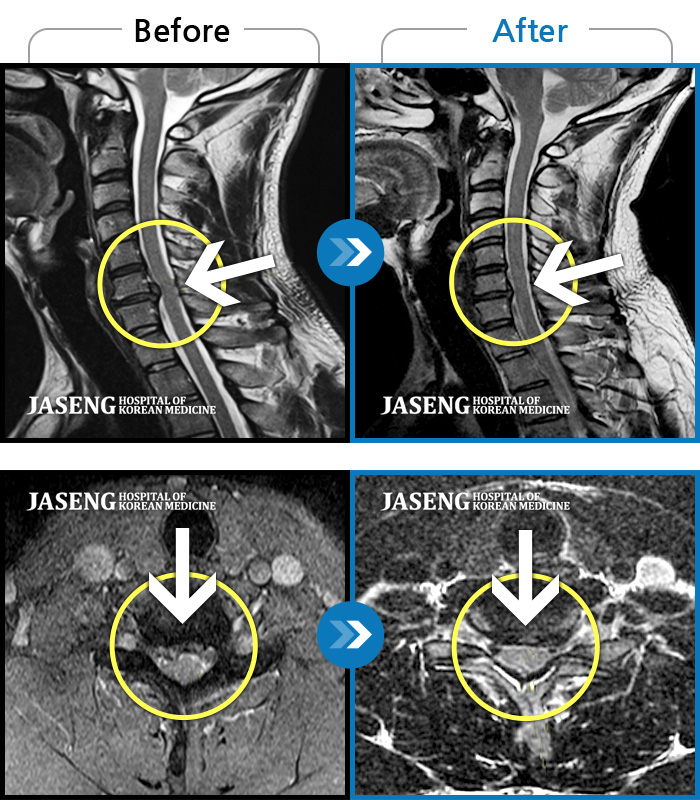

ȯںп Ǹ ǿ ԿǾ, ο ġ ۿ Ƿ ġḦ Ͻñ ٶϴ.